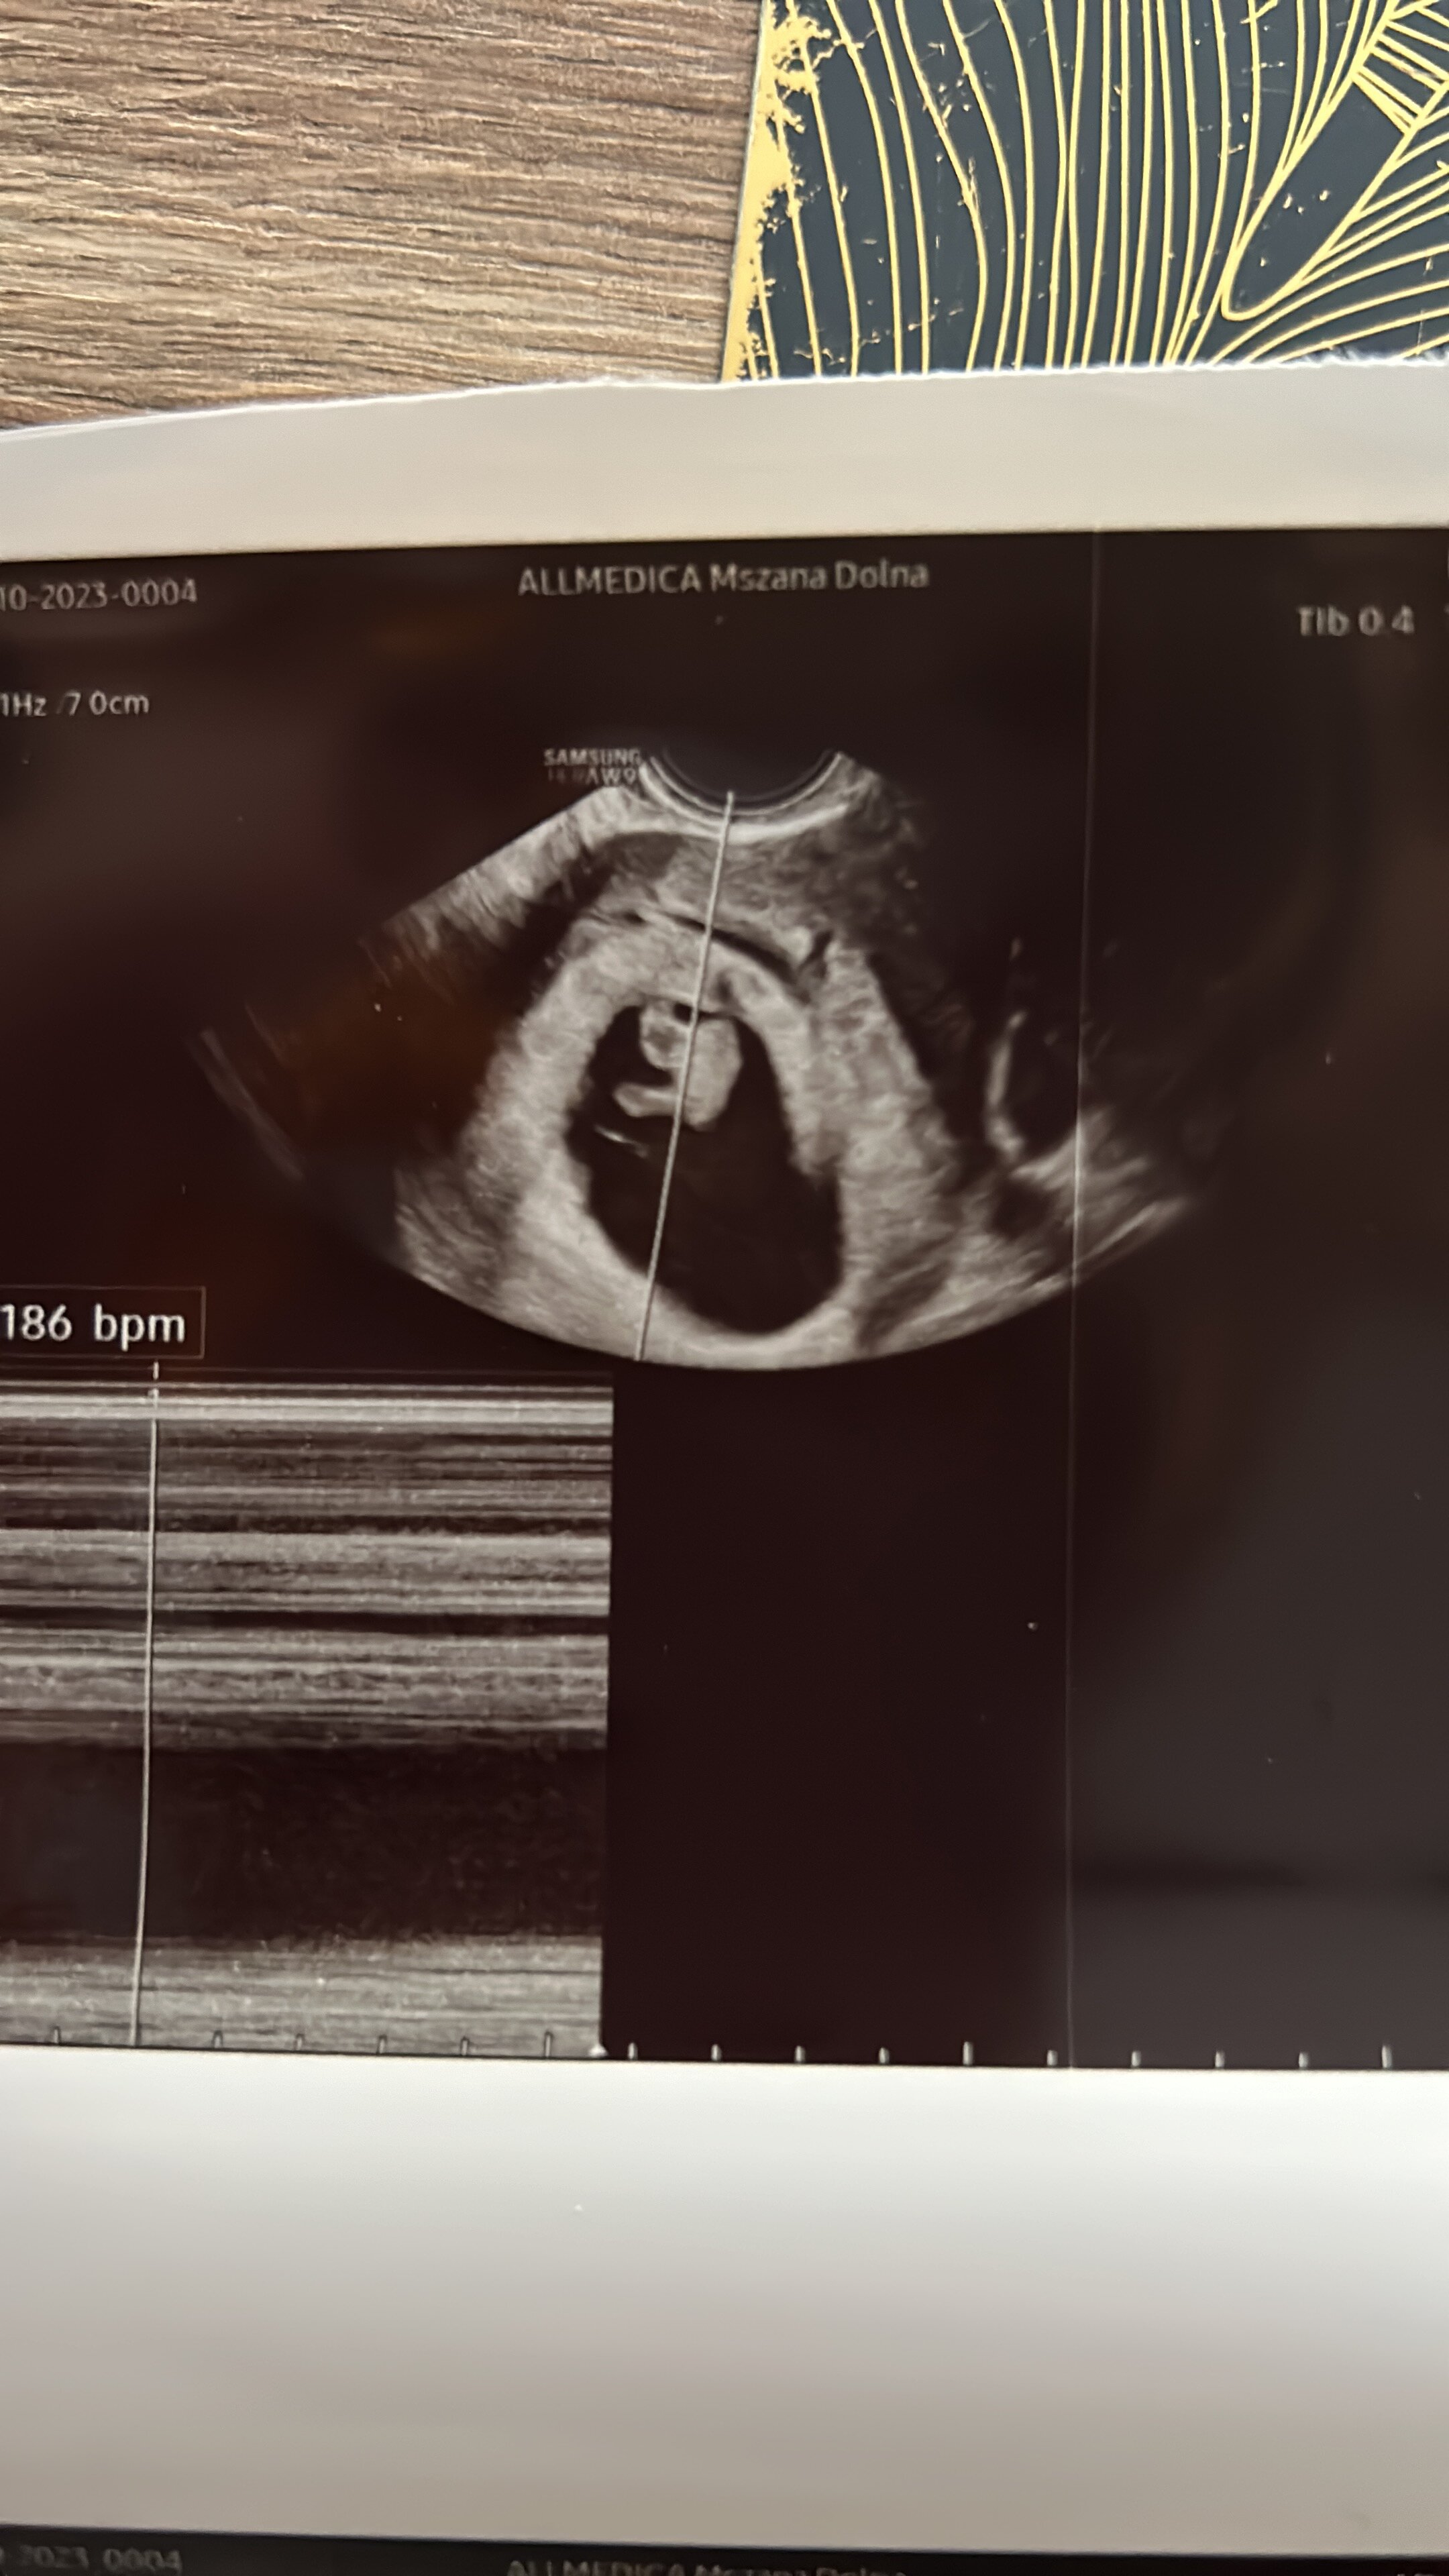

• FFB32DCF-3F33-4373-B24A-D154DCB55CA2.jpeg

FFB32DCF-3F33-4373-B24A-D154DCB55CA2.jpeg

698,6 KB · Wyświetleń: 131